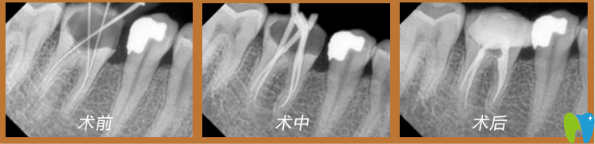

董克文院長(zhǎng)真人案例:

謝先生,33歲,癥狀:牙齒蛀蟲;解決方案:歐式無(wú)痛顯微根管治療。

術(shù)前口述:患上牙髓炎十分痛苦,特別是夜里,劇烈疼痛,吃止疼藥根本不管用,平日吃東西也不敢嚼,人都憔悴了。

術(shù)后感言:治療的時(shí)候醫(yī)生首先在牙齒上鉆一個(gè)洞(打過(guò)麻藥的情況),將炎性分泌物釋放出來(lái),效果立竿見影,馬上就感覺牙齒不疼了。牙疼是病,得治!